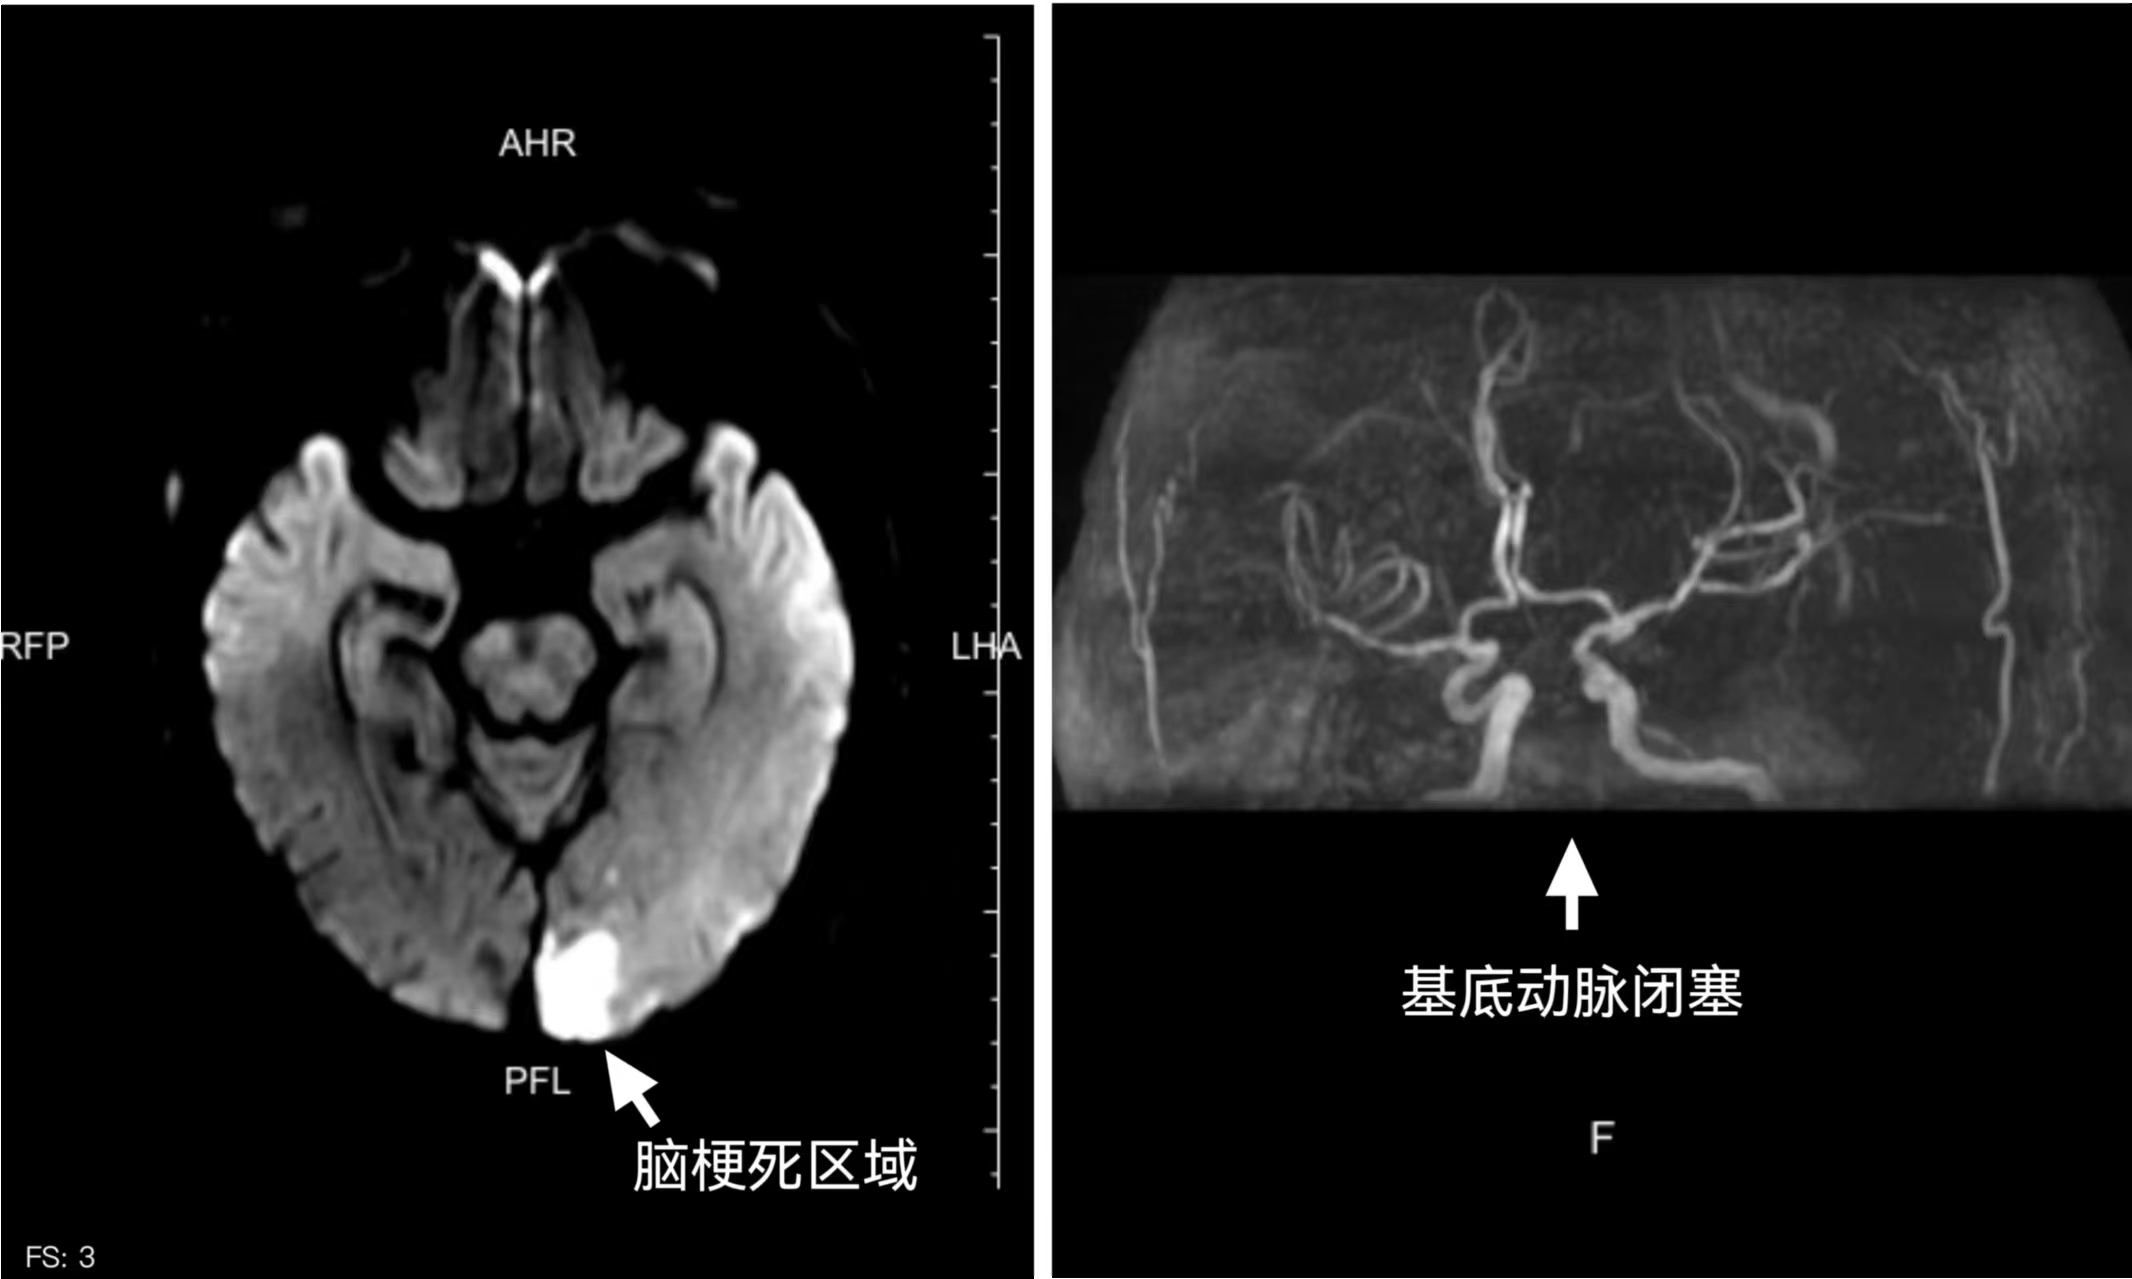

颅脑磁共振检查结果显示患者系脑梗死(左)及基底动脉闭塞(右)。

北院神经内科王丽羽医生已接到院前电话通报,早已在急诊科等候。经过快速评估,迅速判断为急性脑卒中后,立即启动卒中绿色通道,通过快速完善头部CT排除脑出血,确定为急性脑梗死。因为王大爷不能确切地说明发病时间,于是医生对其进行快速急诊颅脑磁共振检查评估,8分钟后结果提示为后脑区多发急性脑梗死病灶,已超过静脉溶栓时间窗,更为棘手的是,掌管呼吸心跳的“生命中枢”——颅内大血管基底动脉已经闭塞。